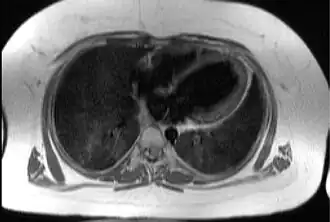

![]() Imagen transaxial del tórax a nivel del corazón, ilustrando la típica capa de tejido adiposo subcutáneo y epicárdico (en blanco) en un paciente con este síndrome. | ||

El síndrome de Alström es una enfermedad hereditaria muy rara que se transmite según un patrón autosómico recesivo, lo que significa que para que un niño la presente debe heredar una copia del gen defectuoso de cada uno de sus padres. Fue descrita en 1959 por Carl Henry Alström y Bertil Hallgren. Los pacientes afectados presentan ceguera, sordera, cardiopatía, diabetes e insuficiencia renal.[1]

Los síntomas principales son déficit de la función cardiaca, pérdida progresiva de visión, diabetes mellitus de comienzo juvenil, obesidad, sordera, retraso del crecimiento e insuficiencia renal.